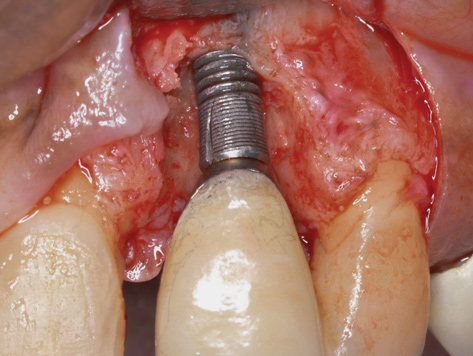

It is important to point out that not all implants presenting with mucogingival or esthetic complications require explantation, especially when the affected implants are partially supporting a multiple-unit restoration. This can be demonstrated in the following case. Implants were placed almost 20 years prior to the patient presenting with advanced soft-tissue recession on the maxillary right arch (Figure 15). There was a lack of keratinized/attached mucosa and buccal bone deficiency. This bone deficiency was not pathologic, but the result of physiologic remodeling,6 which was evident following flap reflection (Figure 16). At the time that these implants were placed, simultaneous bone augmentation to offset the diminution of the arch after tooth extractions was not a prerequisite.7 Also, the importance of soft-tissue augmentation at the time of immediate implant placement was not fully appreciated when this patient was originally treated.8,9 Formation of biologic width combined with a thin periodontal biotype often results in significant crestal bone loss.10 More recently, the importance of increasing soft-tissue thickness as it relates to more favorable crestal bone preservation has been demonstrated by Linkevicius and colleagues.11 Removing these implants would commit the patient to remaking her large prosthesis; therefore, she was interested in maintaining them with a corrective mucogingival procedure.

After gentle debridement with glycine air abrasion and sterile saline, a cross-linked, porcine collagen bone matrix (OSSIX® VOLUMAX; Datum Dental Ltd.) was placed over the buccal aspect of all three affected implants (Figure 17). Next, a subepithelial, connective tissue graft harvested from the right aspect of the patient's hard palate was affixed over the bone scaffold and exposed implants and abutments (Figure 18). And finally, a coronally advanced flap was sutured over the hard- and soft-tissue grafts. The 1-month, follow-up photograph demonstrates incomplete, but significant coverage of the previously exposed implants and abutments (Figure 19).

Due the loss of crestal bone in 360 degrees around these implant platforms, it is unrealistic to anticipate complete coverage of the implant abutments and collars.12 This procedure arrested the progress of recession, regenerated some of the lost facial bone, and increased the zone of keratinized mucosa.

(19.) At 1-month postoperatively, partial coverage of the exposed abutments/implant platforms has occurred. There is now a band of keratinized mucosa, and the patient is instructed in nontraumatic plaque removal protocols. Follow-up to monitor long-term maintenance of the regenerated keratinized mucosa is encouraged.

Figure 19